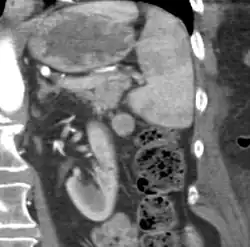

Gross pathology of an accessory spleen -